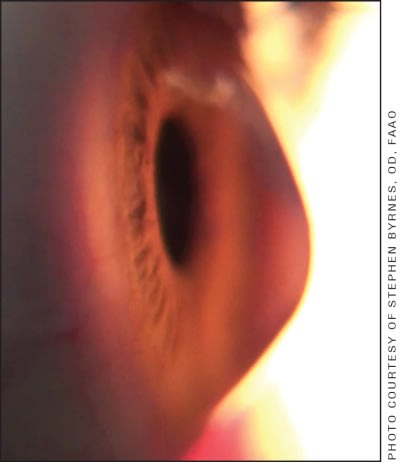

Consistent with previous years, there has been tremendous growth in large-diameter lens fitting and in the availability of large-diameter lens designs. The overriding premise is that these lenses provide significantly enhanced stability by vaulting over diseased, ectatic (Figure 4), or irregular corneas and can provide consistent comfort and visual performance for some of our most challenging contact lens patients.

Figure 4. Advanced keratoconus.